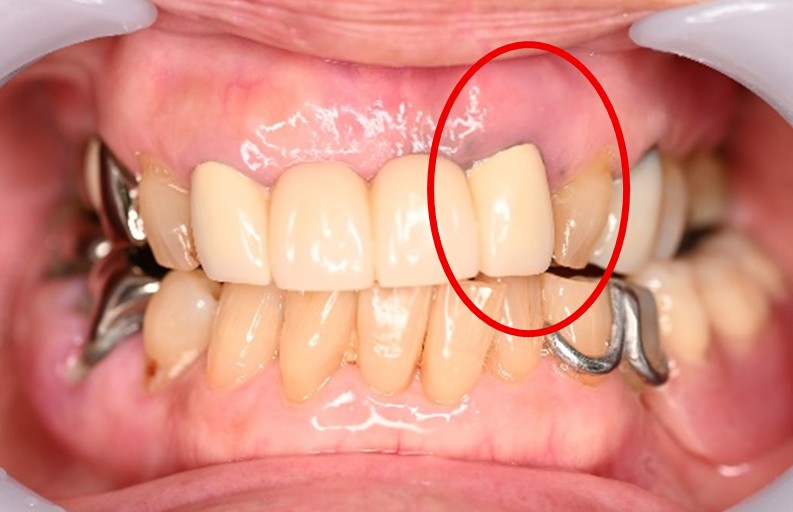

歯根が破折していましたので、抜歯しました。抜歯後、金属のバネが見えない入れ歯を希望されましたので、スマートデンチャーをいれました。腫れている歯の隣、ブリッジになっているところの歯のつけ根のところが茶色くなっているのできれいにしたいというお話でしたので、ブリッジを取り除き新しいものを被せなおしました。

所感

治療後「口元がきれいになり、とても嬉しいです。」と、とても喜んでくださいました。